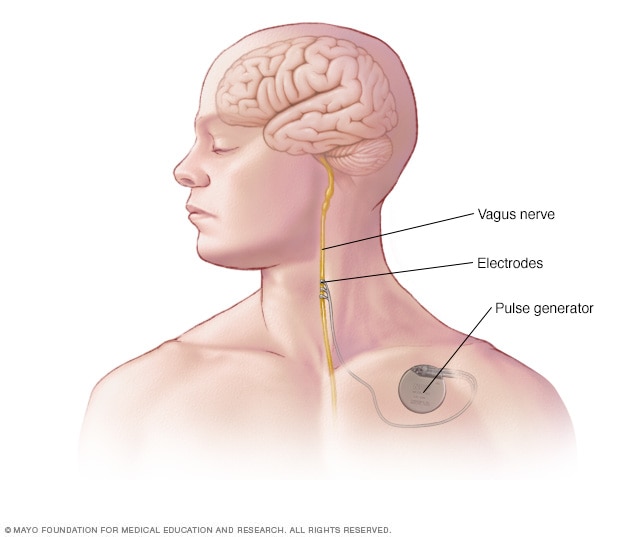

Implanted vagus nerve stimulation

In vagus nerve stimulation, a device placed under the skin of the chest stimulates the vagus nerve in the neck. This sends signals to the brain that lessen seizures.

-

Vagus nerve stimulation. Vagus nerve stimulation may be an option when medicines haven't worked well enough to control seizures and surgery isn't possible. A device called a vagus nerve stimulator is implanted underneath the skin of the chest, similar to a heart pacemaker. Wires from the stimulator are connected to the vagus nerve in the neck.

The battery-powered device sends bursts of electrical energy through the vagus nerve and to the brain. It's not clear how this inhibits seizures, but the device can usually reduce seizures by 20% to 40%.

Most people still need to take anti-seizure medicine. But some people may be able to lower their medicine dose. Vagus nerve stimulation side effects may include throat pain, hoarse voice, shortness of breath or coughing.